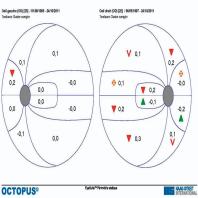

- eFig. 10-15 - Suivi en périmétrie automatisée standard et en Matrix™ d'un sujet de 63 ans présentant un déficit débutant